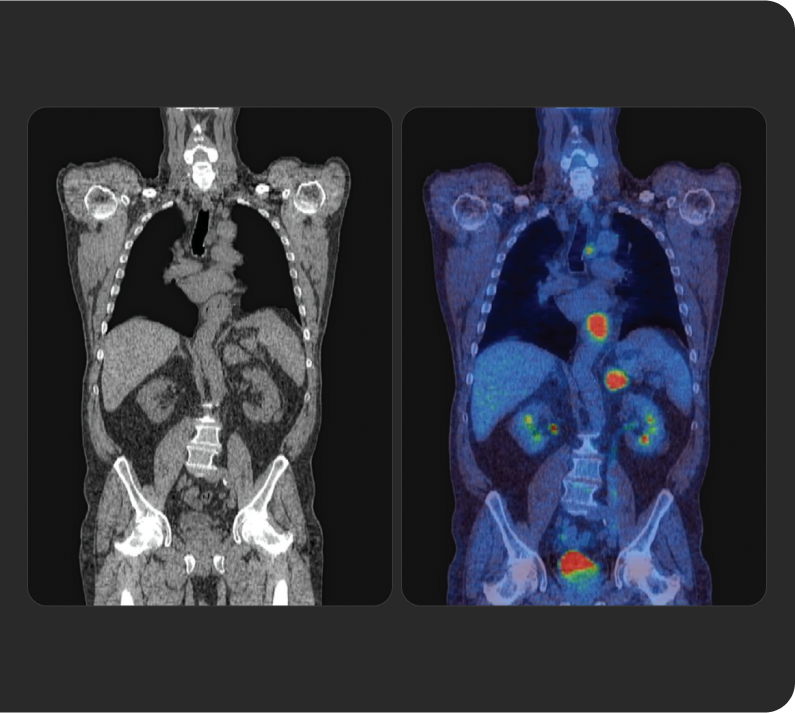

Tratar o que se vê

Os radioligandos podem ter uma finalidade e aplicação diagnóstica e terapêutica, permitindo uma abordagem teranóstica, que pode ser traduzida pela afirmação "tratar o que se vê e ver o se trata" (do inglês "see what you treat and treat what you see"). 1b 4 5

A ciência

RLT representa uma evolução em direção ao tratamento de precisão

RLT é uma abordagem de medicina de precisão que reconhece e trata diretamente a doença, com um foco particular nos cancros avançados.

Recorrendo ao poder dos átomos radioativos, RLT é capaz de dirigir radiação às células-alvo em qualquer parte do corpo.7a 8a